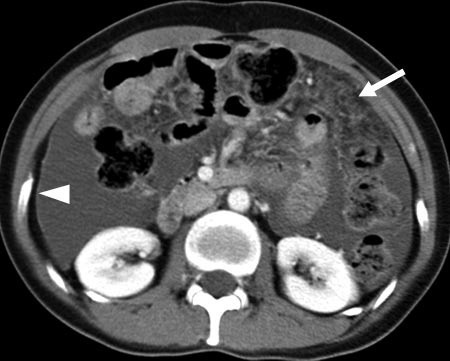

복부 내에 퍼진 결핵, 결핵성 복막염

결핵은 결핵균에 감염되어 발생하는 만성감염 질환입니다. 결핵균은 주로 폐를 침범하지만, 뼈, 뇌, 신장, 심장 등 다른 장기에도 침범할 수 있습니다. 결핵성 복막염은 결핵균에 감염되어 복막에 염증이 생기는 질환입니다. 복막은 복강 내 기관을 싸고 있는 막으로, 결핵균에 감염되면 복막에 염증이 생기고, 복수가 차는 증상이 나타납니다.